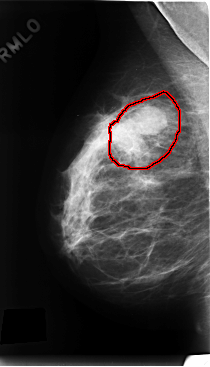

C_0197_1.RIGHT_MLO

RIGHT_MLO LINES 4768 PIXELS_PER_LINE 2728 BITS_PER_PIXEL 12 RESOLUTION 50 OVERLAY

FILE: C_0197_1.RIGHT_MLO.OVERLAY

TOTAL_ABNORMALITIES 1

ABNORMALITY 1

LESION_TYPE MASS SHAPE LOBULATED MARGINS ILL_DEFINED

ASSESSMENT 4

SUBTLETY 5

PATHOLOGY MALIGNANT

TOTAL_OUTLINES 1

BOUNDARY